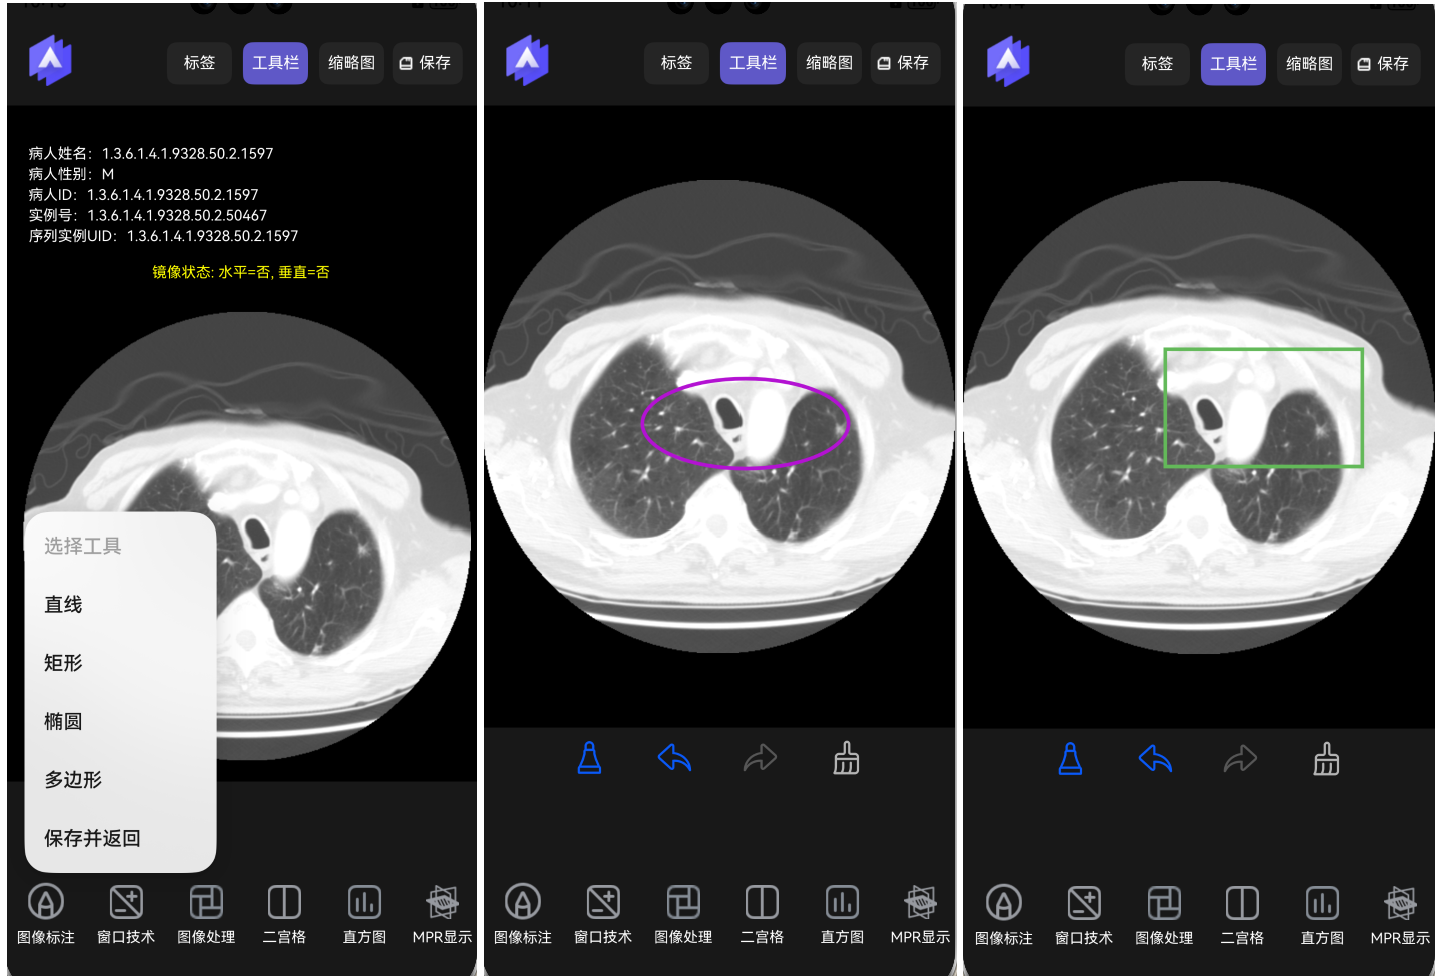

二宫格显示。以两个宫格方式显示2张图像,如下图所示。